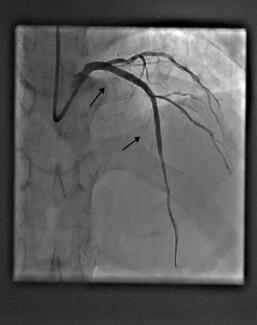

Abdul Wahab, MD; Sachin Joseph, MD; Andres Vargas-Estrada, MD

The authors share a case of a large LAD-to-right-sided coronary cameral fistula that produced angiographic coronary steal but no significant shunt, allowing for successful conservative management.